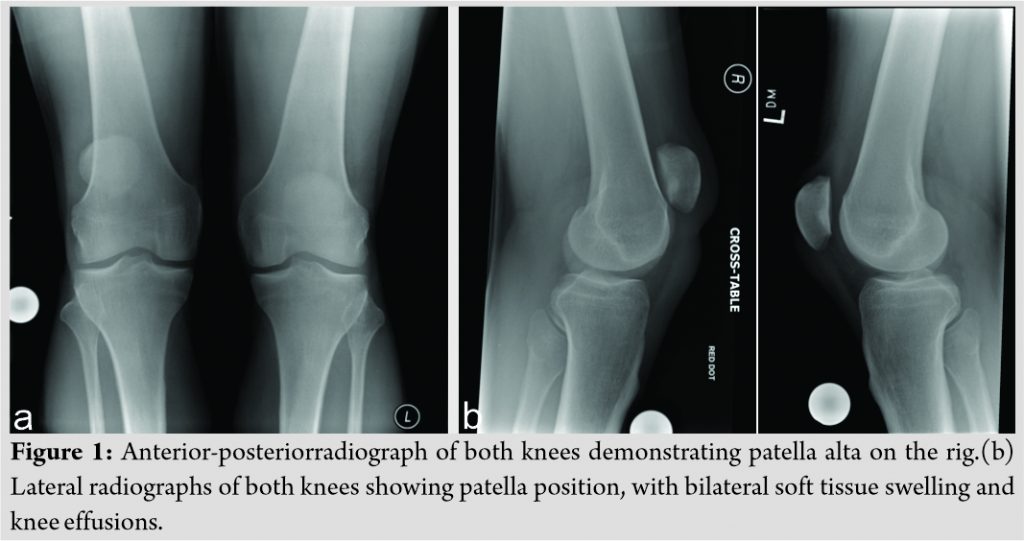

On examination, he had a palpable defect in his extensor mechanism proximal to the patella on the left and distal to the patella on the right. He was unable to straight leg raise bilaterally and had no power in knee extension. His plain radiographs (Fig. 1) demonstrated a knee effusion with normal patella height on the left and a knee effusion with an elevated patella on the right. A diagnosis of quadriceps tendon rupture on the left and patellar ligament rupture on the right was made.